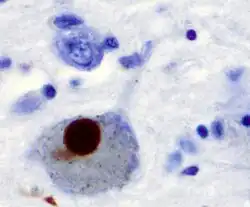

The main pathological characteristic of Parkinson's disease is cell death in the substantia nigra. In particular, this death occurs in the ventral part of the pars compacta, with up to 70% of the cells affected by the time the patient dies.[2] The mechanisms by which the brain cells are lost are varied.[3] One mechanism consists of an abnormal accumulation of the protein alpha-synuclein bound to ubiquitin in the damaged cells. This protein accumulation forms inclusions called Lewy bodies.[2]

The disease begins in structures of the lower brainstem and the olfactory system. In particular, the dorsal motor nucleus of the vagus nerve in the medulla oblongata and anterior olfactory nucleus are affected.[6] Lewy neurites, thread-like alpha-synuclein aggregates, are more prevalent than globular Lewy bodies in this stage.[4]

In addition to the pathology observed in Stage 1, Stage 2 is characterized by additional lesions in the raphe nuclei and gigantocellular reticular nucleus of the medulla oblongata.[4][6] The disease then moves up the brainstem, traveling from the medullary structures to the locus ceruleus in the pontine tegmentum. Similar to Stage 1, Lewy neurites outnumber Lewy bodies.[4]

At the beginning of Stage 3, the disease has entered the substantia nigra and Lewy body lesions begin to form in the pars compacta.[4][6] The latter half of this stage involves disease progression into the basal nucleus of Meynert, a cluster of acetylcholine-rich neurons in the basal forebrain.[6] Further, structures affected in Stages 1 and 2 begin to develop more Lewy bodies.[4]